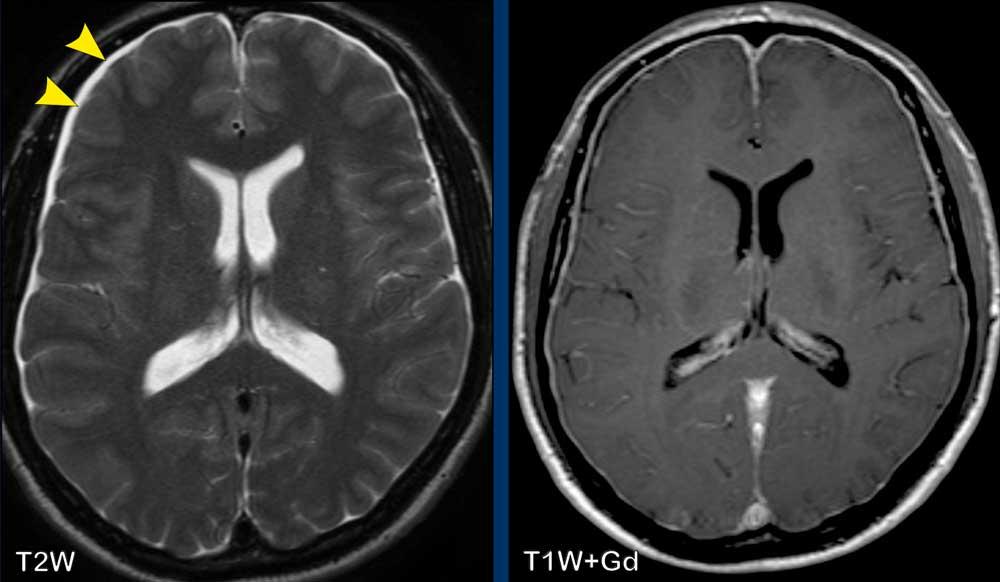

Các hình ảnh này của một bệnh nhân nam 44 tuổi, nhập viện với triệu chứng đau đầu kéo dài, tăng lên khi cúi người về phía trước.

Chuỗi xung T2W cho thấy tụ dịch dưới màng cứng hai bên nhỏ (đầu mũi tên).

Sau khi tiêm gadolinium có ngấm thuốc màng cứng đều đặn.

Có sự ứ máu các cấu trúc tĩnh mạch, thể hiện ở xoang dọc trên (đầu mũi tên), xoang thẳng và hợp lưu xoang.

Có sự dịch chuyển xuống dưới của thân não với rút ngắn khoảng cách cầu-vú, dẹt cầu não và gập góc thân não tại chỗ nối sọ-cổ.

Đám rối tĩnh mạch trong khoang ngoài màng cứng phía trước cổ bị giãn rộng.

Kết luận

Các dấu hiệu này điển hình cho hạ áp lực nội sọ.

Bệnh nhân sau đó được chẩn đoán mắc rối loạn mô liên kết.